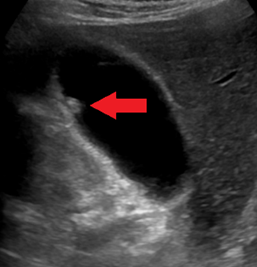

• 복부 초음파 (DOC)

담석과의 감별 필요 → 내강내 돌출, 체위 변경에도 이동하지 않음, posterior accoustic shadowing 없음